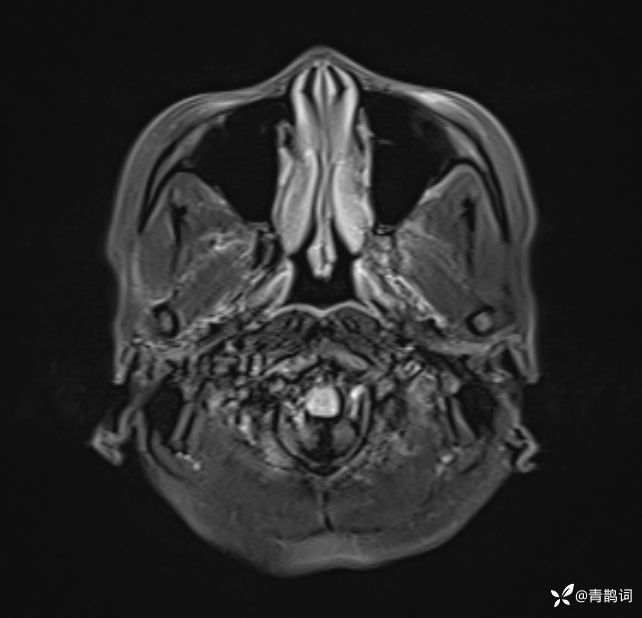

入院后完善磁共振:

T2: